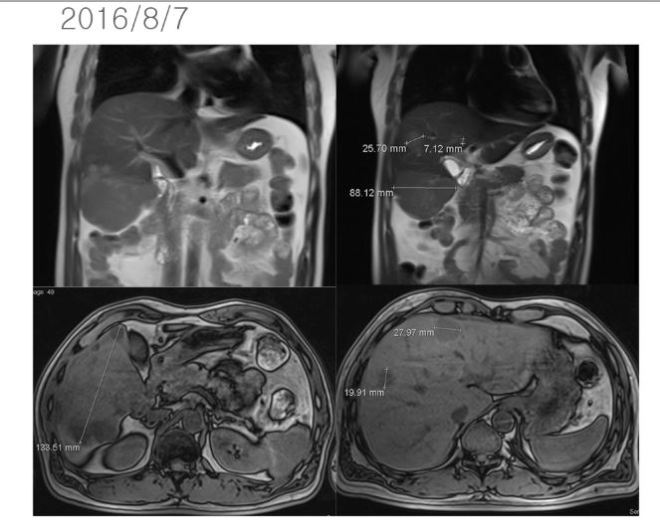

47세의 남자인 이 환자는 젊어서부터 담배를 피기 시작하였는데 20년간 거의 하루 한 갑이상을 피웠고 최근에 경제사정이 나빠지자 스트레스로 하루 2 갑씩을 피웠다고 한다. 그런지 1년이 되어서 복통을 느껴서 검진 결과 간암(hepatocellular carcinoma)으로 복부에 임파전이가 있고 여러 개의 작은 암덩이와 함께 제일 큰 간암의 크기는 약 11cm 정도로 판명되었다(2016/7/9).

이후 8월 7일 MR상 거의 간의 우엽에 14cm 가까이 되는 종양이 보이는데 그 사이에 암이 3cm 이상 자랐다는 이야기가 된다. 이후 K 의료원에서 넥사바라고 불리우는 sorafenib을 2달 동안 사용하였다. 이후 결과는 간의 종양은 약간 자랐다고 볼수 있고 간암의 수치는 많이 떨어졌다고 하였다.